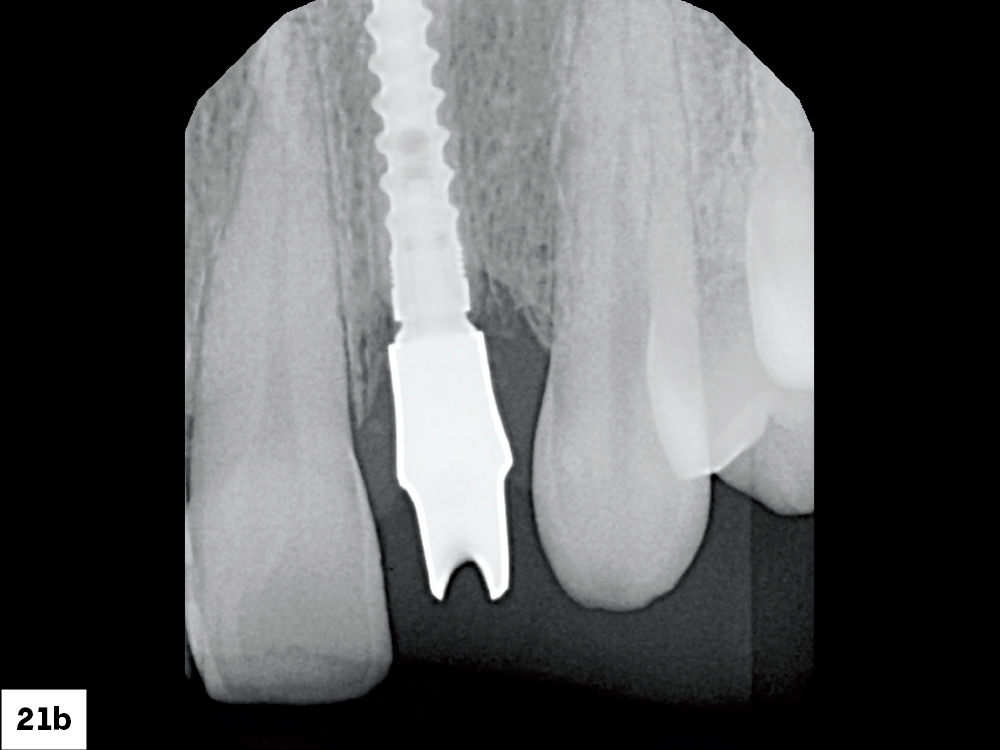

The abutment was tried in to verify the marginal position and then hand-tightened into place. An X-ray was then taken to ensure the abutment was fully seated. Because a 3.0 mm Glidewell HT implant was placed, the abutment was torqued to 15 Ncm.

Figures 21a, 21b: The abutment was tried in to verify the marginal position and then hand-tightened into place. An X-ray was then taken to ensure the abutment was fully seated. Because a 3.0 mm Glidewell HT implant was placed, the abutment was torqued to 15 Ncm.